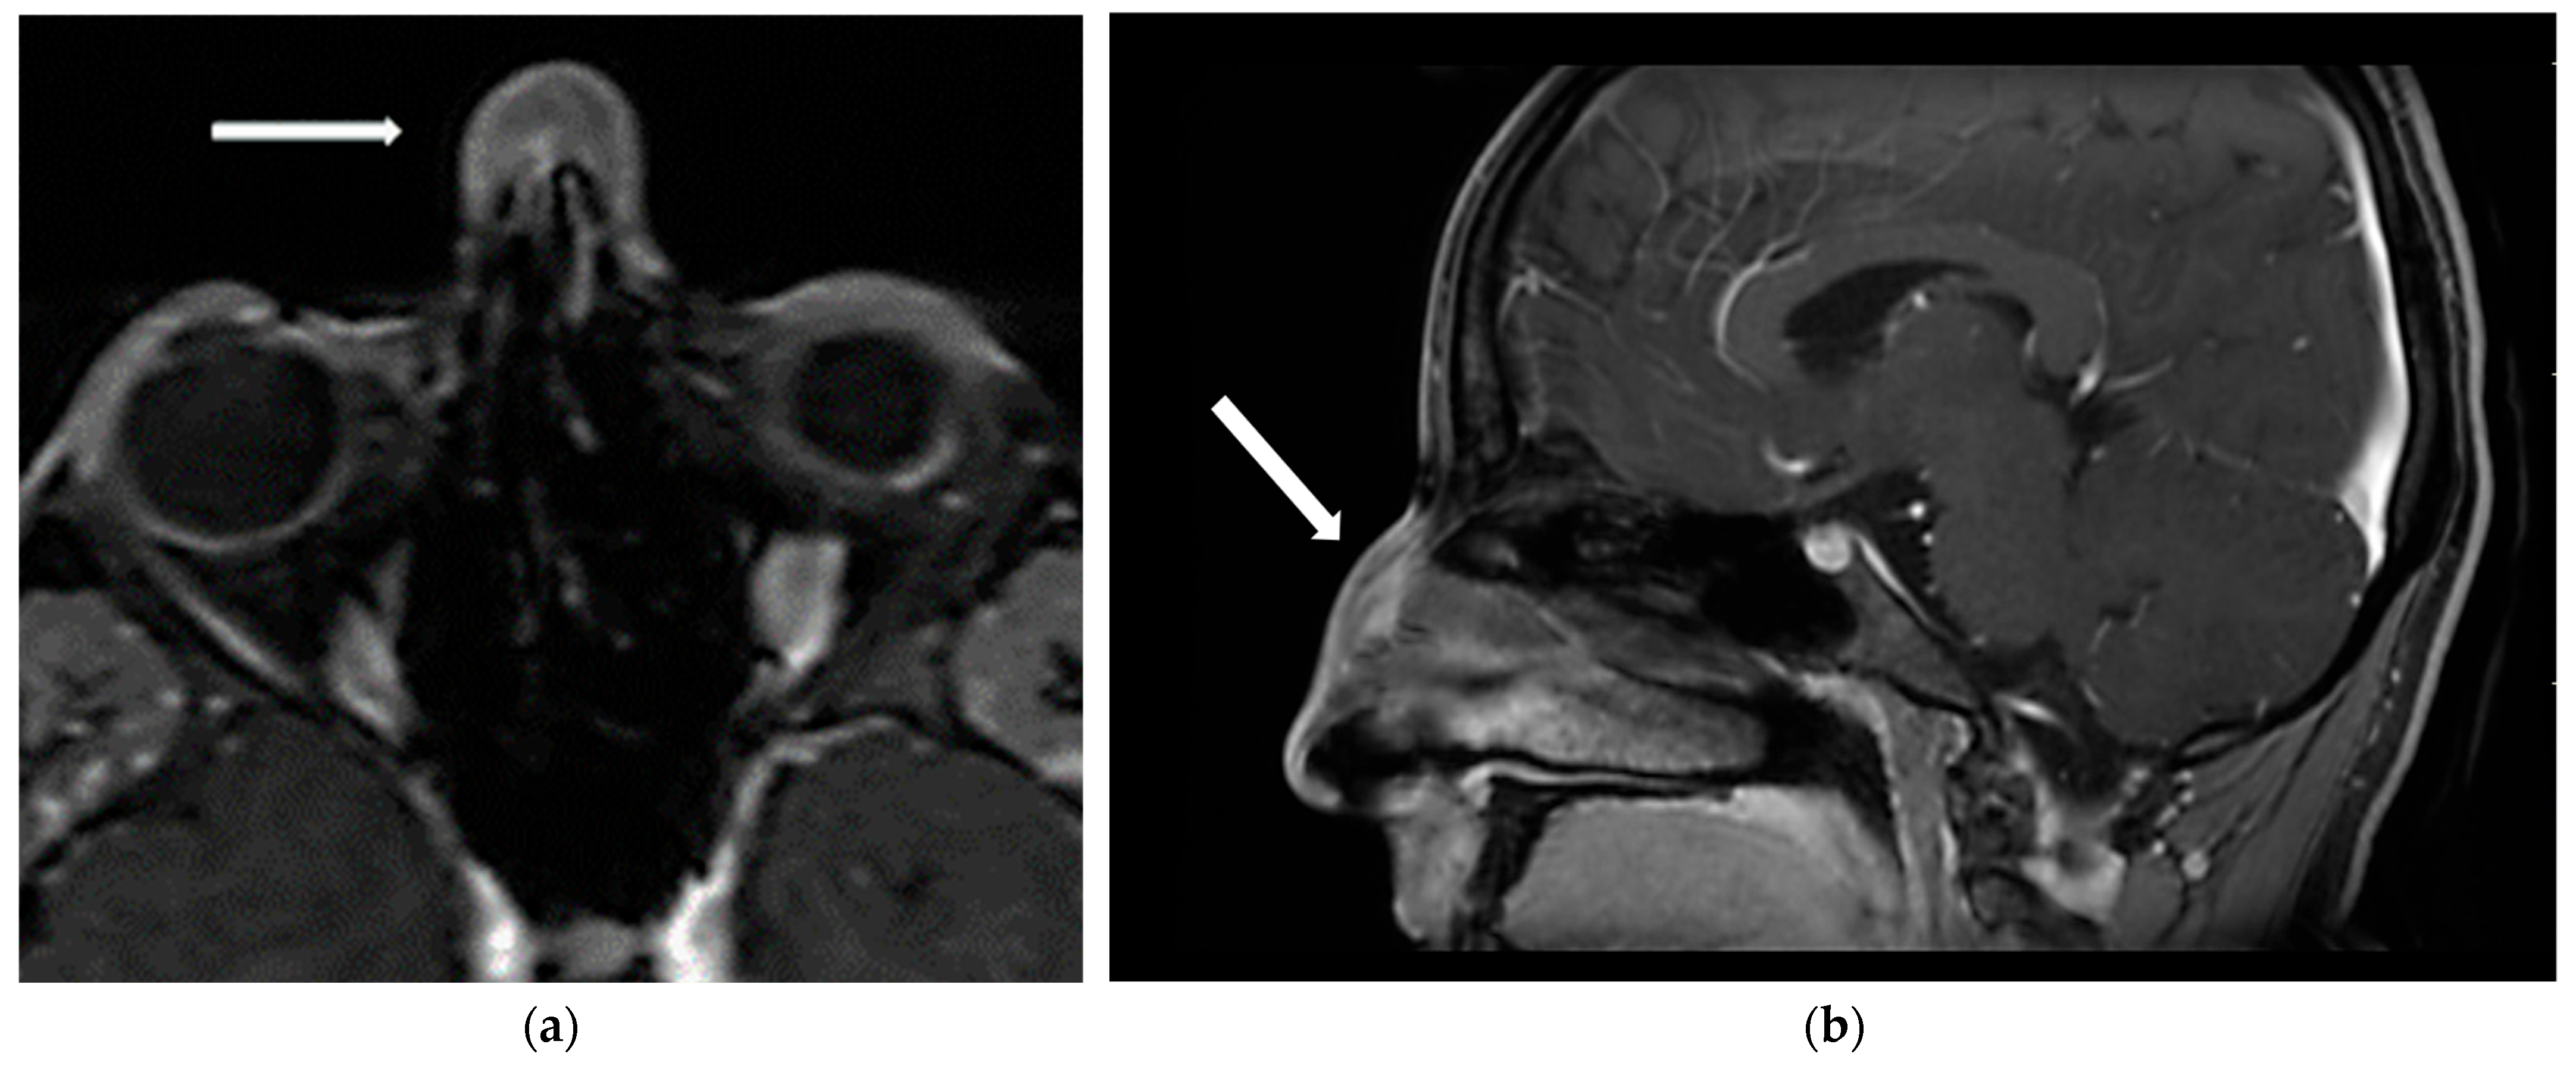

2.2. Investigations